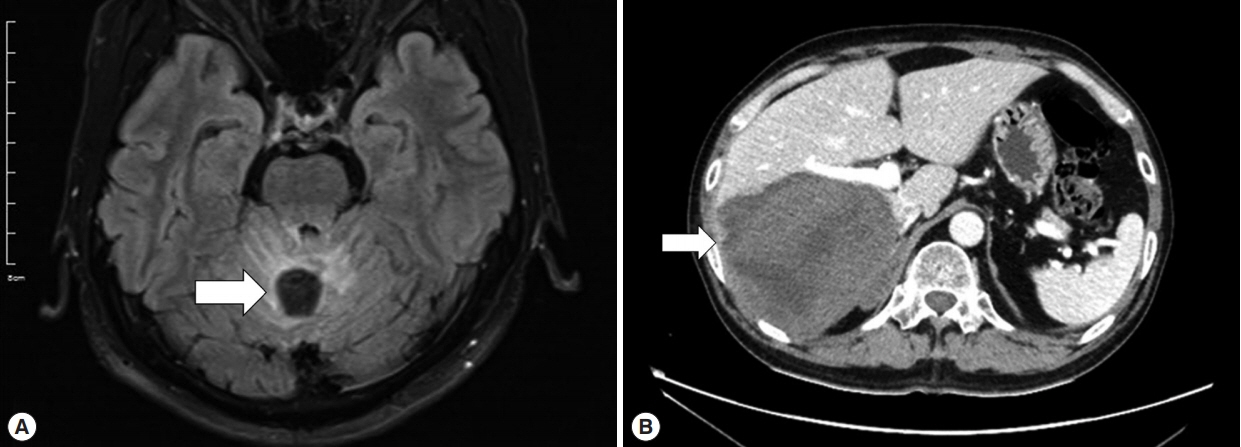

In August 2018, the patient visited our hospital because of worsening symptoms. This was the third university-affiliated hospital he had visited during the course. At admission, his vital signs and laboratory tests were all within normal limits except for mild elevation of eosinophils (white blood cell count 9,190/μl; segment neutrophils 66.2%, lymphocytes 20.9%, eosinophils 5.8%). Although IgG for cysticercosis was positive again (titer 0.704; cut-off 0.232) by ELISA [7], the diagnosis of neurocysticercosis was doubted because the size and shape of cysts in the liver, lung and brain were not consistent with those of cysticercosis using radiological approaches. Given the past travel history to endemic areas of echinococcosis and the multiple organ involvement of cysts with varying sizes, a serum ELISA for echinococcosis IgG was performed as previously described [8], and turned out to be positive (titer 0.886; cut-off 0.270). The patient was finally diagnosed as probable cystic echinococcosis based on the diagnostic criteria [9]. Since it was technically difficult to excise all lesions from both cerebellar hemispheres and the temporal lobe, albendazole, 400 mg twice a day (10–15 mg/kg/day), was started. Worried about paradoxical worsening of neurological symptoms after the commencement of the treatment, we prescribed 4 mg of dexamethasone 4 times a day for 3 days, and then it had been tapered off over 10 days. His dizziness and dysarthria are gradually improving, and the cerebellar lesions are also radiologically improving at 2 (Fig. 4A, B) and 7 months (Fig. 4C, D) after the commencement of the therapy.

Fig. 4

Treatment response on the intracranial lesions. The brain MRI T2 sequencing images showing slight improvement of cystic lesions and perilesional edema (arrow) (A, B) in October 2018 and (C, D) in March 2019.

Fig. 4 Treatment response on the intracranial lesions. The brain MRI T2 sequencing images showing slight improvement of cystic lesions and perilesional edema (arrow) (A, B) in October 2018 and (C, D) in March 2019.